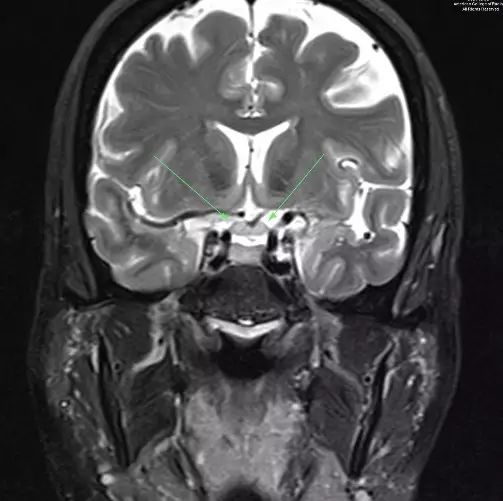

图 1. 冠状T2示视神经增粗(箭头示)

图 2. 增强T1示视交叉增粗并强化(箭头示)